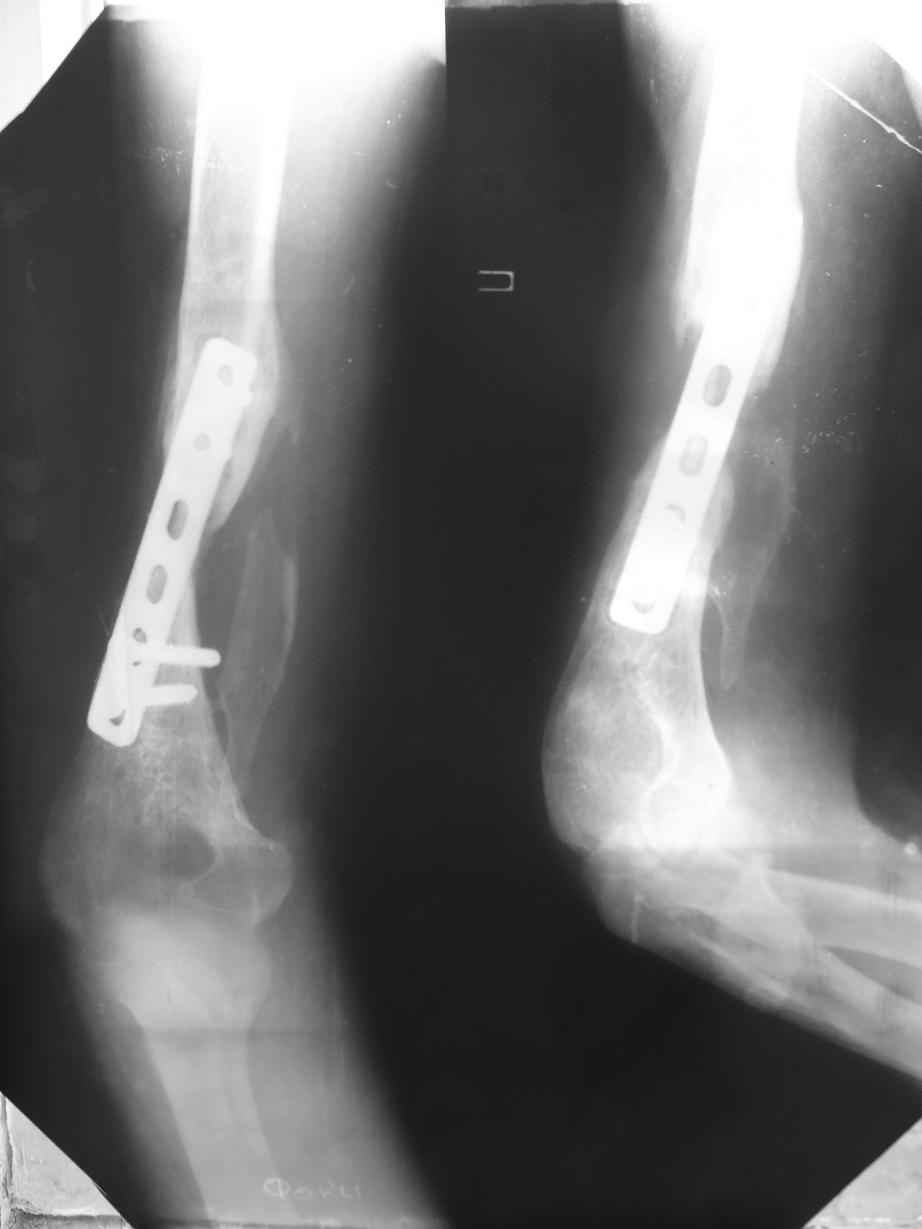

Биологические стимуляторы типа Synthes chronOS мы

применяем только для закрытия дефекта в закрытом

пространстве, например в тибиал плато, пилоне и

ацетабулярных переломах.

Несмотря на то, что компания рекомендует, что препарат является остеоиндуктивным, но мы считаем, что препарат надо применять для заполнения дефектов, потому что "indicated for use in bony voids or gaps that are not intrinsic to the stability of the bony structure.

chronOS is indicated for use treatment of bony defects created surgically or through traumatic injury".

А для стимулирования мы применили массу из состава:

OP1 с деминерализованной костью, добавив к ним еще

красную часть, приготовленную из крови больной.

Взятая перед операцией кровь в количестве 80 мл

провели через центрифугу и без сывороточной части

красную матрицу добавили к остальным.

С такой массой наверное ложный сустав "over killed", но надеюсь, что-то из них при такой фиксации окажет стимулирующее действие.